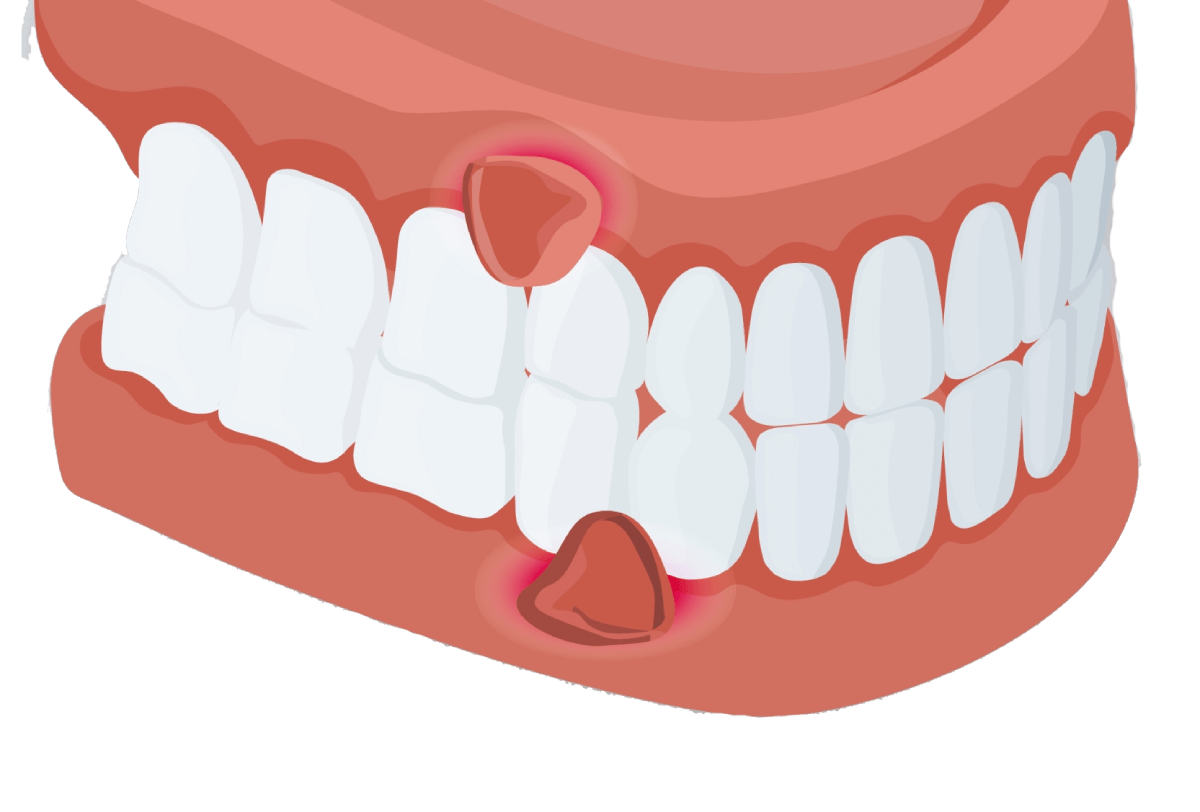

Gum Swelling

Gum swelling, which is frequently accompanied by bleeding gums and touch sensitivity

What are Gum Swelling ?

Gum swelling is most frequently brought on by poor oral hygiene, pregnancy, and infections. It is frequently accompanied by bleeding gums and discomfort to the touch. There are numerous home remedies for treating gum inflammation, which is frequently caused by plaque and tartar around the teeth and gums.